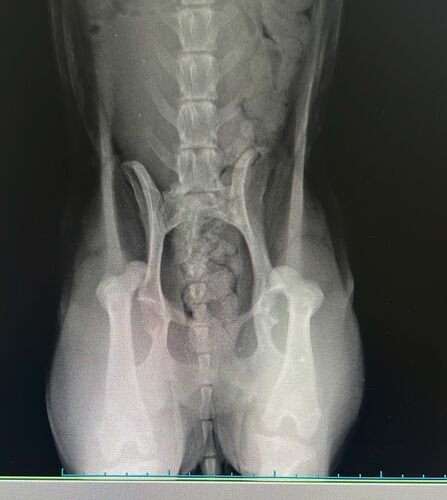

Na semana passada, durante aquela forte chuva de quarta-feira, uma manilha se rompeu e a água invadiu a nossa casa, Houve muitas perdas materiais, mas o que mais nos entristeceu foi o ocorrido com a a nossa cachorrinha Sussu. No dia seguinte, assustada com a tempestade, ela pulou de uma laje com 5 metros de altura, resultando no deslocamento de ambos os fêmures. Agora, ela precisa passar por uma cirurgia no valor de R$3.850,00.